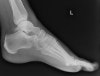

X-ray : 삼각골증후군(Os trigonal syndrome, Os trigonum, Posterior process fx)

X-ray 사진상으로 경계에 경화상이 보이면 오래된(진구성) 골절일 가능성이 큽니다.

거골 후방돌기 골절(posterior process fx)은 Shepherd fracture로 불리는데, 가성관절이 되면 삼각골과의 감별이 어렵습니다.